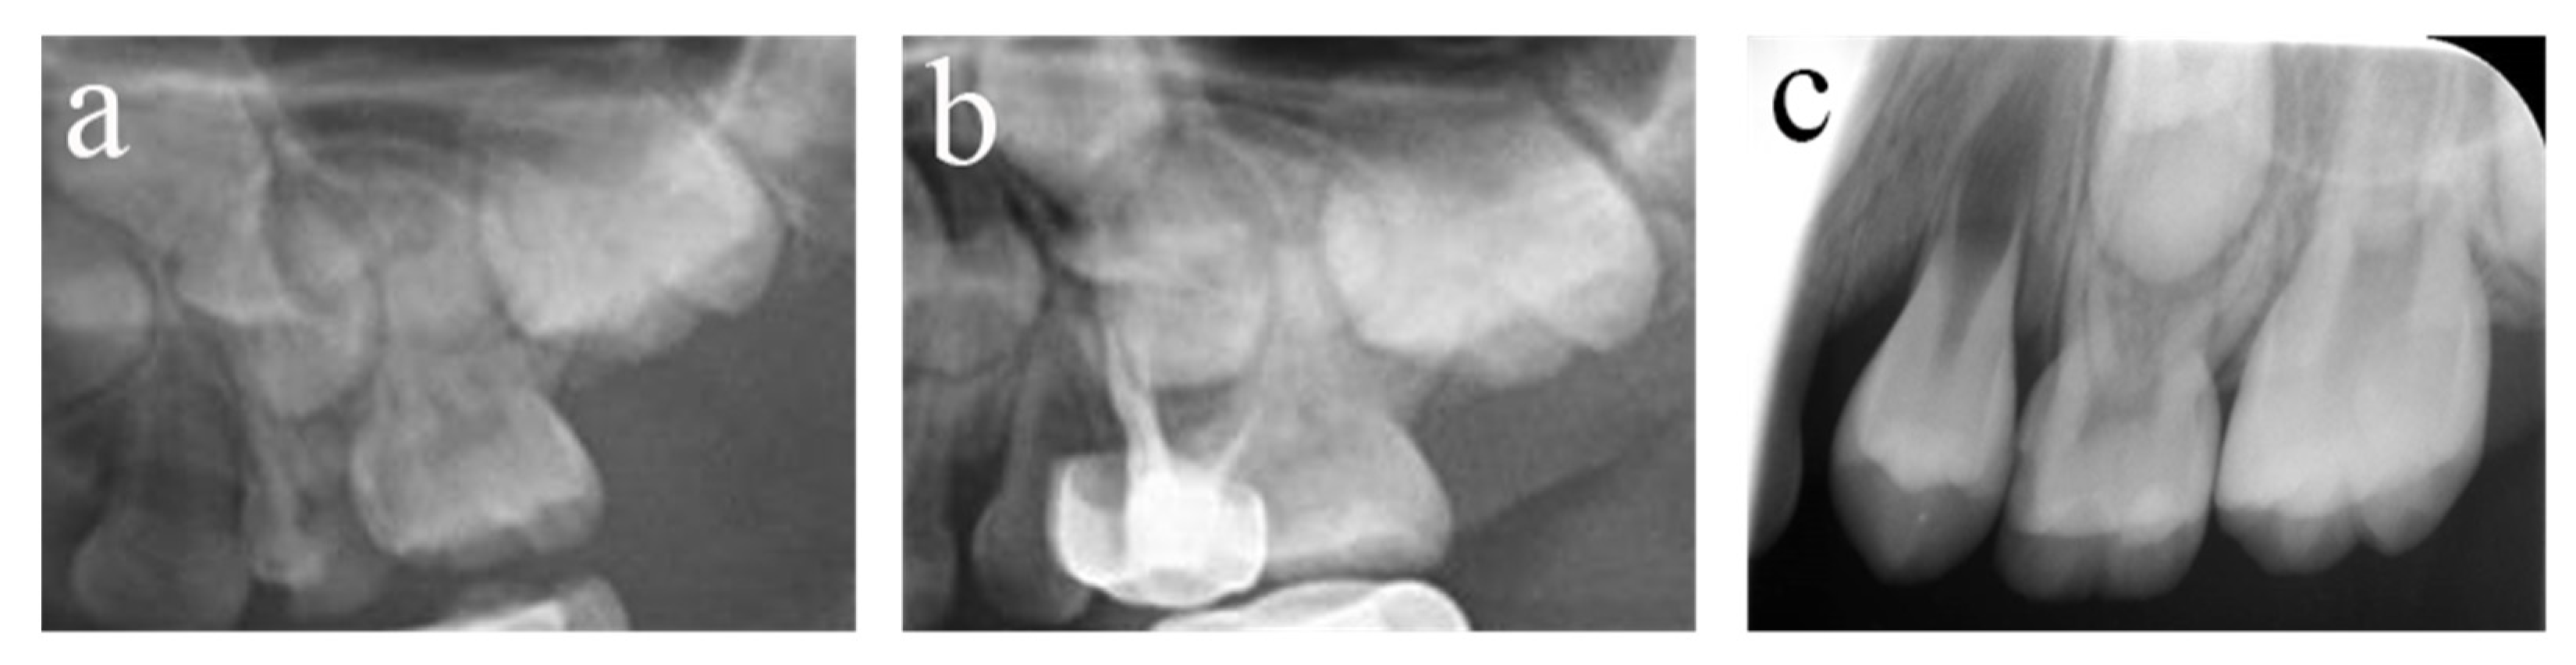

Figure 4.

#51, #61, and #62 received pulpectomies under DGA with a 12-month follow-up period (57-month-old female child). (a) Preoperative radiograph and #61 revealed periapical radiolucency. (b) Two weeks later, the postoperative radiograph showed underfilling in #61 and optimal filling in #51 and #62. (c) Radiograph taken 12 months postoperatively showing nothing abnormal about #62 and a periapical radiolucency surrounding the root apical of #51. Moreover, a radicular cyst occurred surrounding the apical root of #61, and the eruption direction of #21 was altered. Pulpectomies in #62 succeeded but failed in #51 and #61.